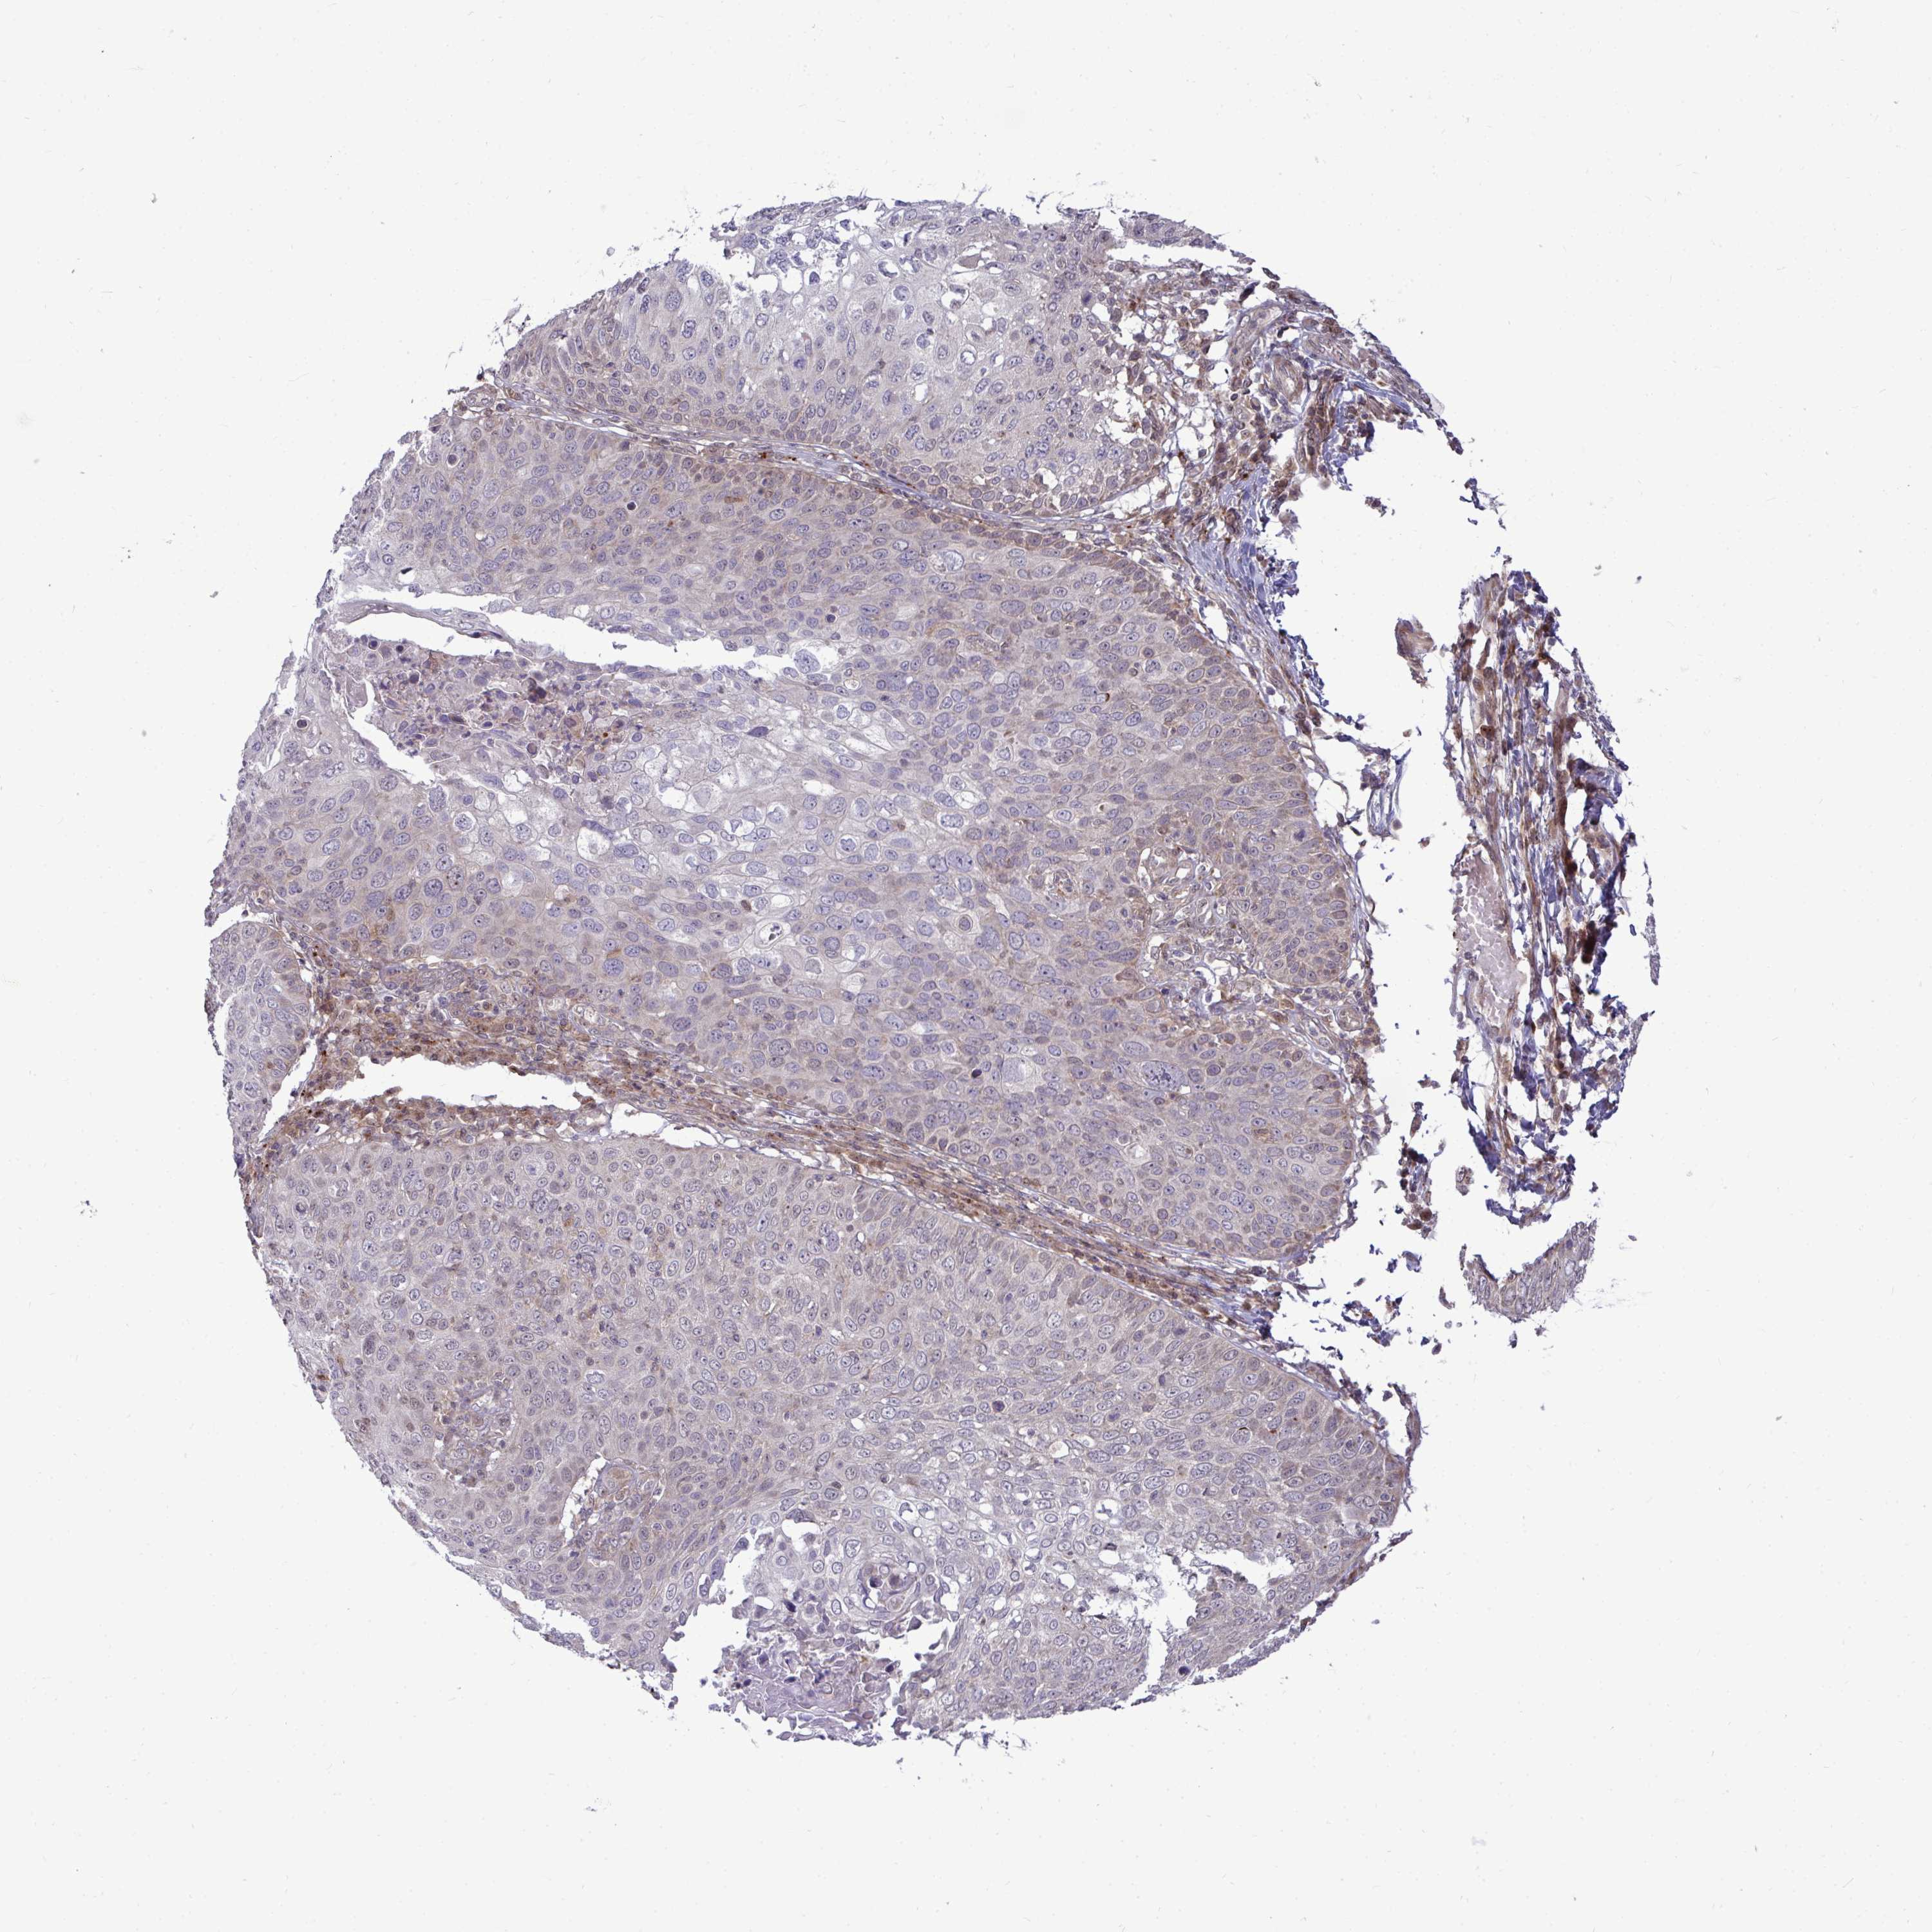

SKIN CANCER - Protein expressioni

A mouse-over function shows sample information and annotation data. Click on an image to view it in a full screen mode. Samples can be filtered based on level of antibody staining by selecting one or several of the following categories: high, medium, low and not detected. The assay and annotation is described here.

Antibody stainingi

Antibody staining in the annotated cell types in the current human tissue is reported as not detected, low, medium, or high, based on conventional immunohistochemistry profiling in selected tissues. This score is based on the combination of the staining intensity and fraction of stained cells.

Each image is clickable and will lead to virtual microscopy that enables deeper exploration of all samples and also displays staining intensity scores, fraction scores and subcellular localization as well as patient and tissue information for each sample.

Antibody HPA057633

Staining

High

Medium

Low

Not detected

Intensity

Strong

Moderate

Weak

Negative

Quantity

>75%

75%-25%

<25%

None

Location

Nuclear

Cytoplasmic/membranous

Cytoplasmic/membranous,nuclear

Basal cell carcinoma

Squamous cell carcinoma, NOS